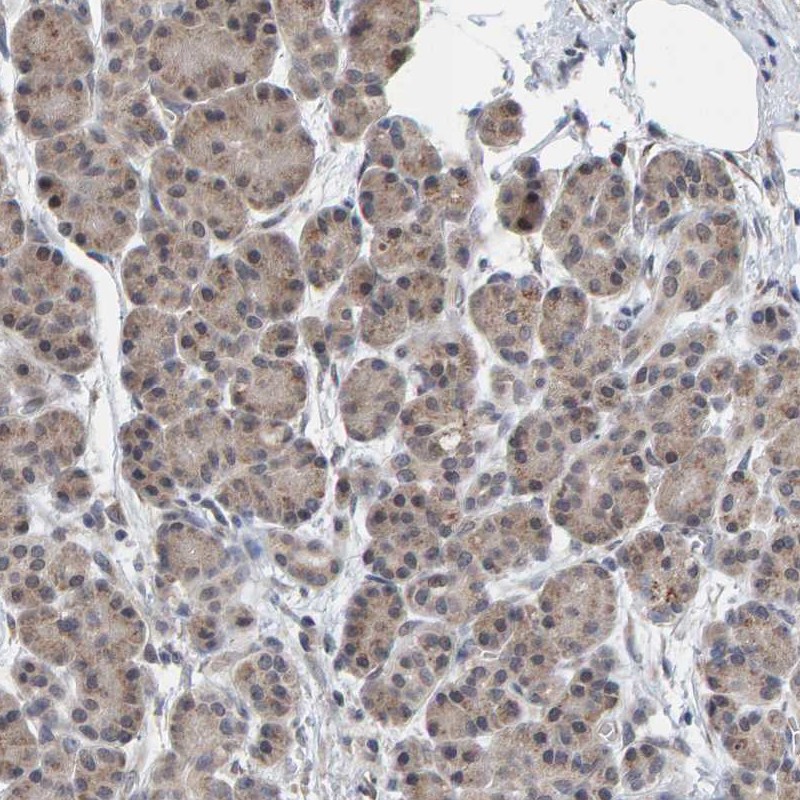

Immunohistochemistry analysis in human kidney and pancreas tissues using Anti-SCRN2 antibody. Corresponding SCRN2 RNA-seq data are presented for the same tissues.